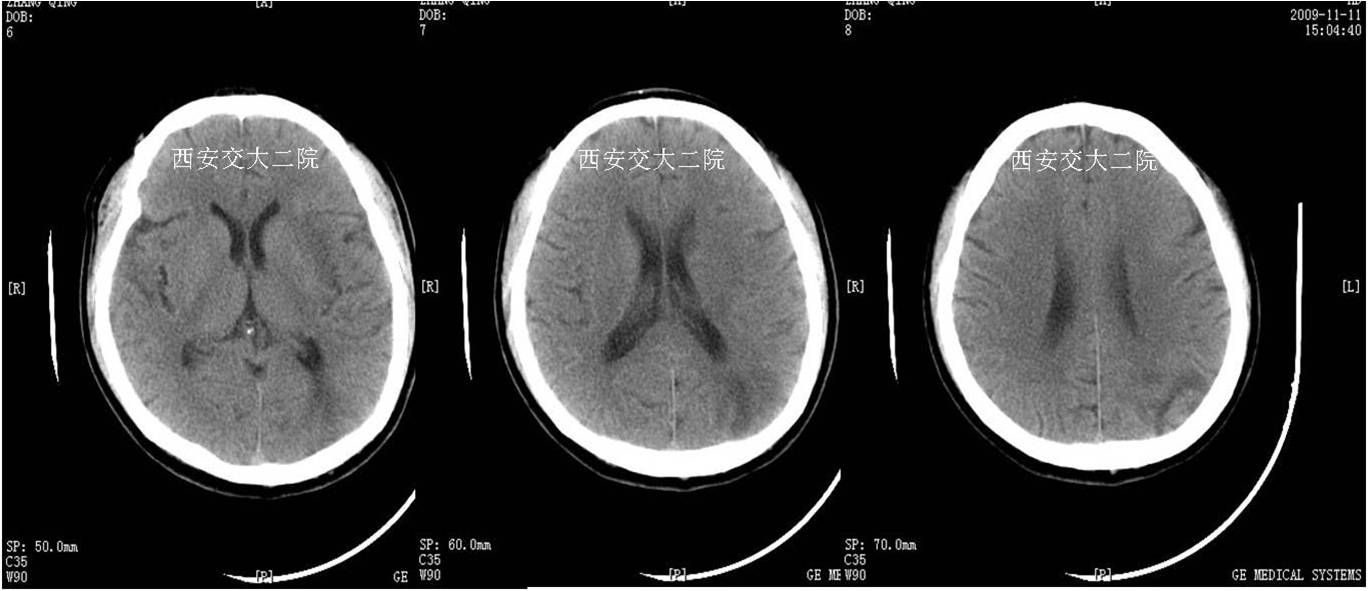

术后即刻CT

术后5天脑CT